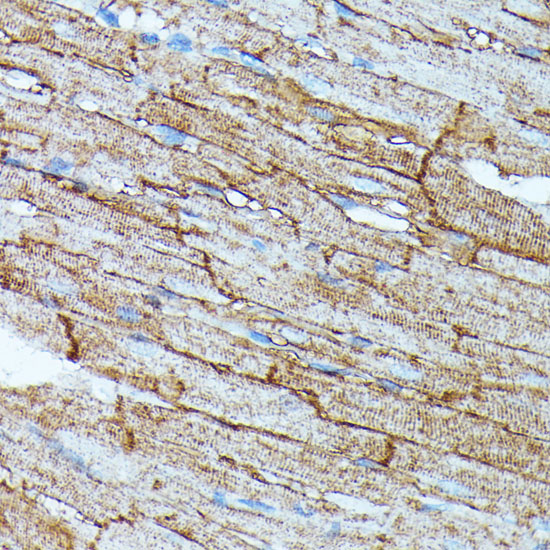

Immunohistochemistry of paraffin-embedded rat heart using SLC14A1 at dilution of 1:100 (40x lens).